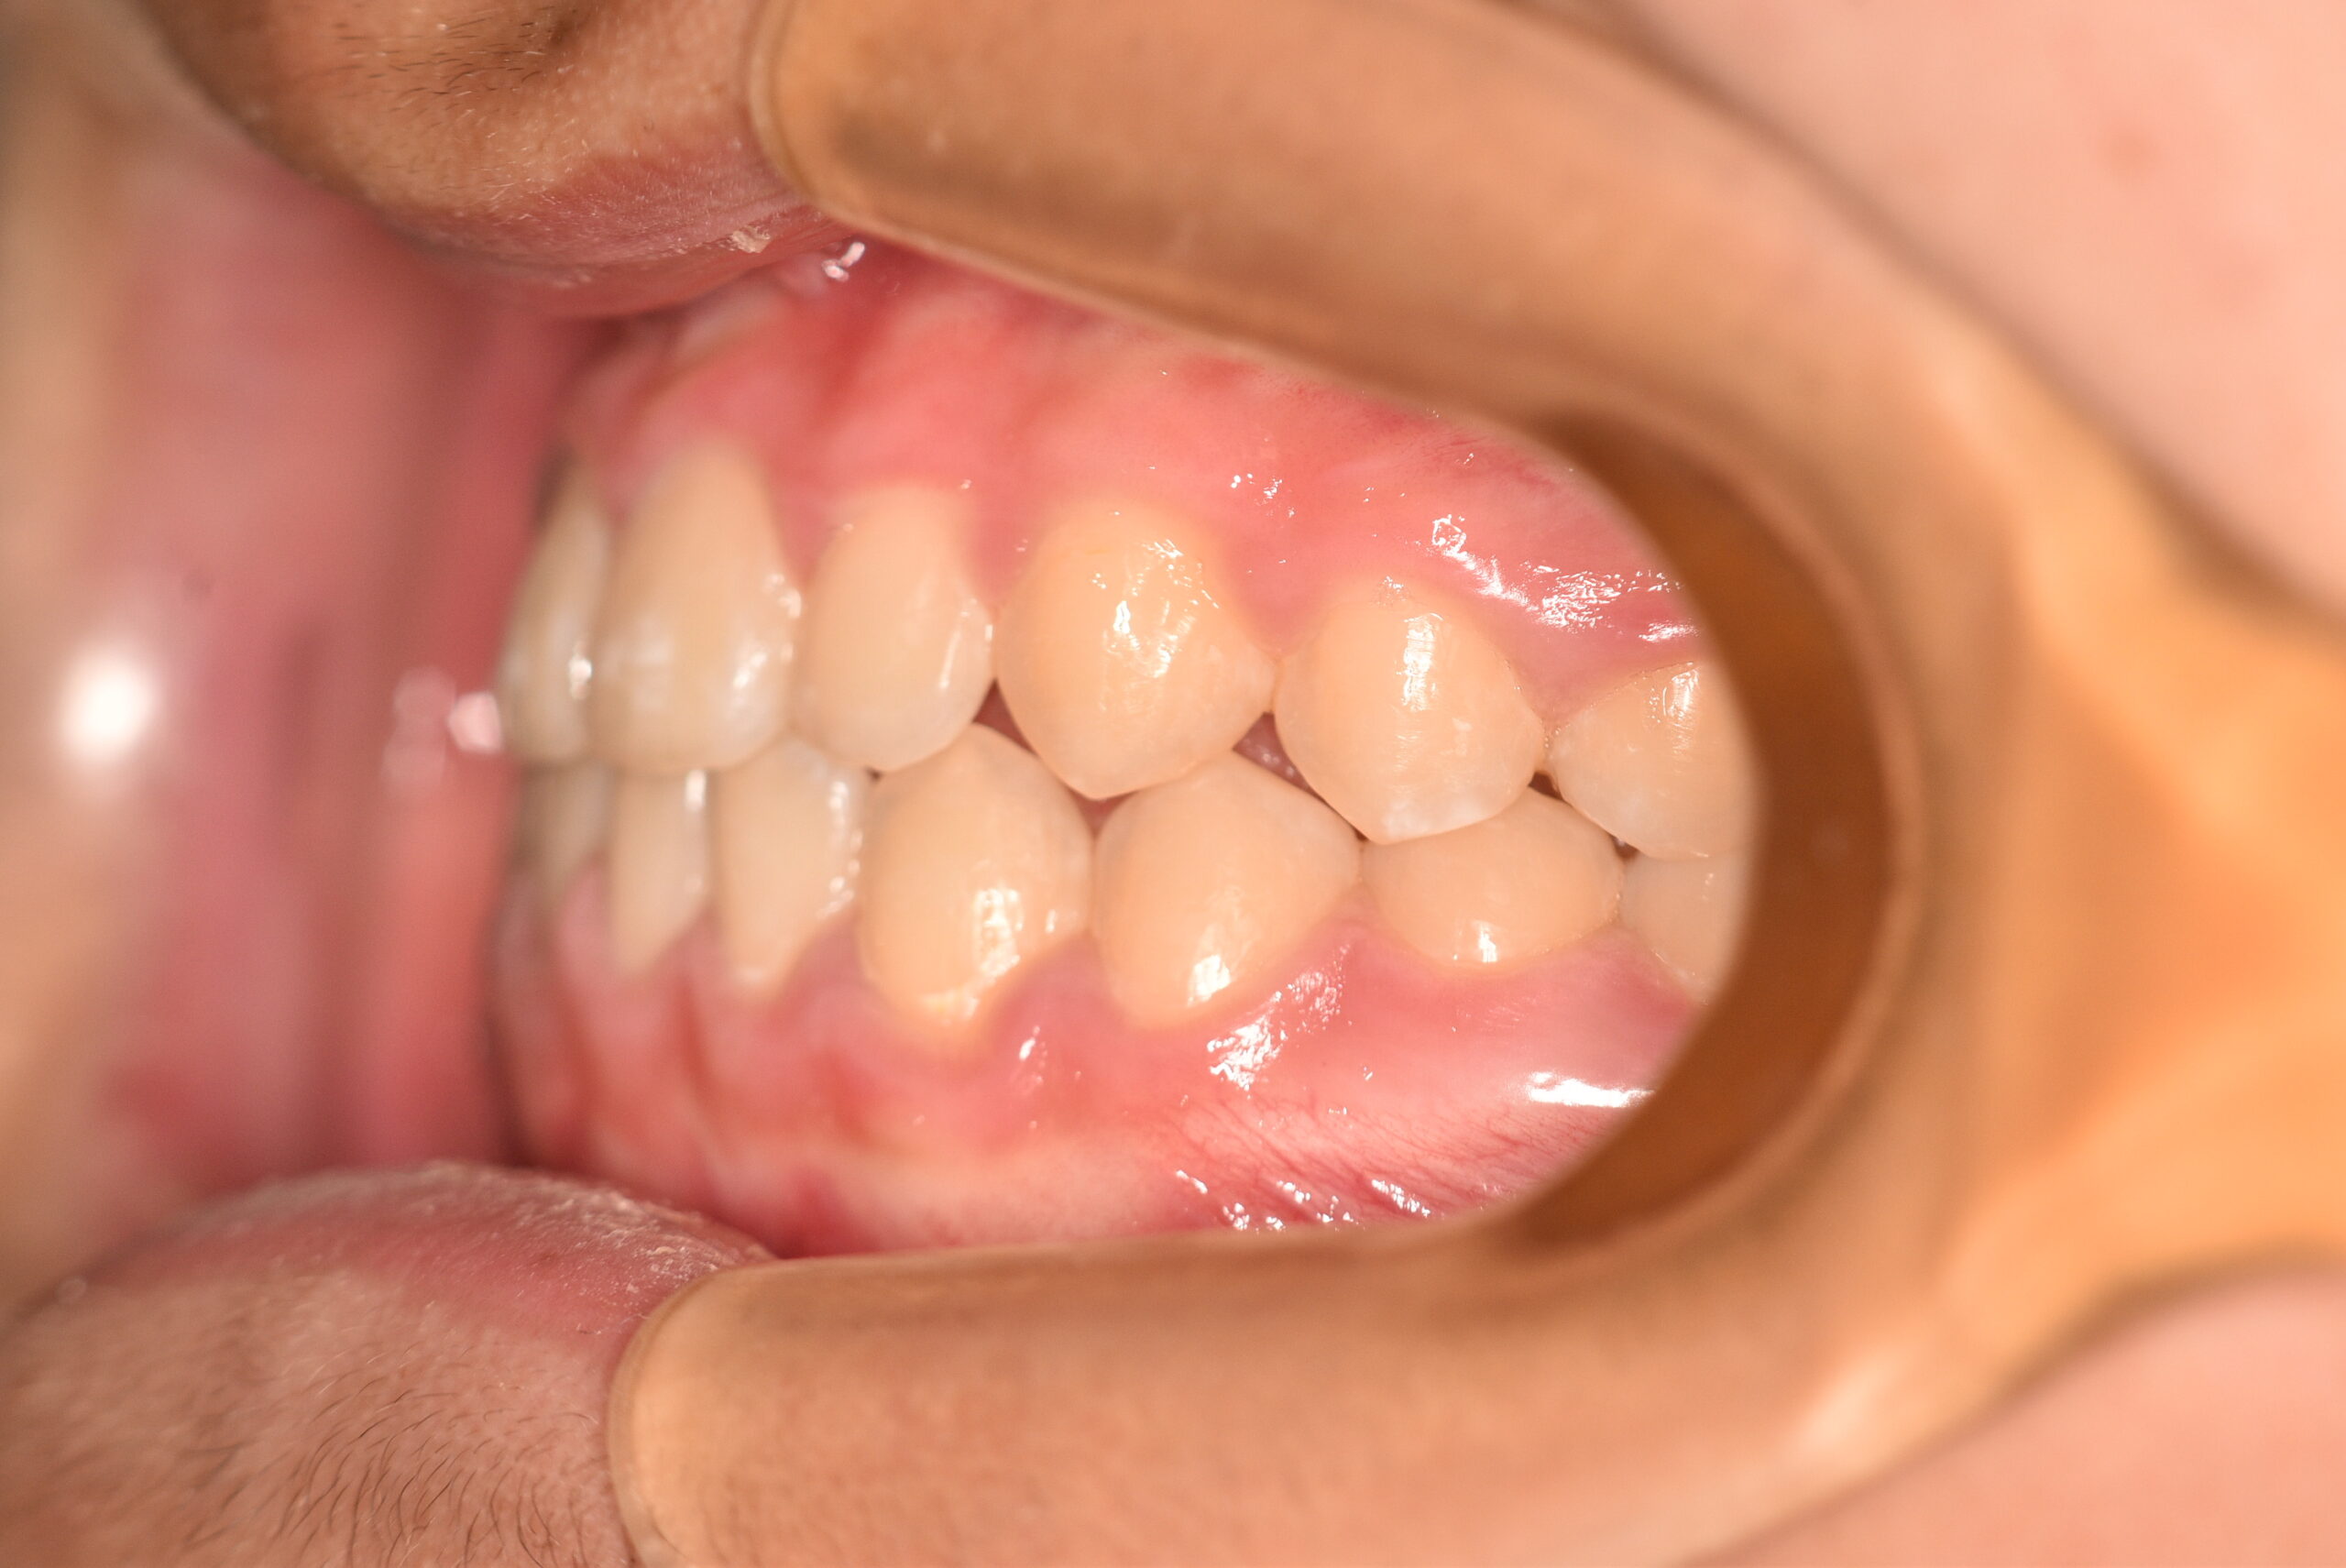

反対咬合(非抜歯)[2015]

初診時

年齢

6歳0ヶ月 性 別 男性

治療期間 7年3ヶ月 費 用 矯正施術料:750,000円 調整料:4,000円

治療内容の詳細 初診時6歳の男性で、受け口を気にされ来院されました。

検査の結果、反対咬合を伴うアングルⅢ級不正咬合と診断しました。

治療としては、初期段階の治療として、機能的矯正装置で鼻呼吸の獲得と舌の位置や口唇の閉鎖といった筋機能習癖の改善を行い、上顎前方牽引装置を使用し上顎骨の前方方向への発育を誘導し、反対咬合の改善を行いました。

永久歯列に交換後、非抜歯の上、セルフライゲーションブラケット装置(デーモンシステム)で歯の配列と咬合関係の改善を行いました。

治療期間は、7年3ヶ月でした。